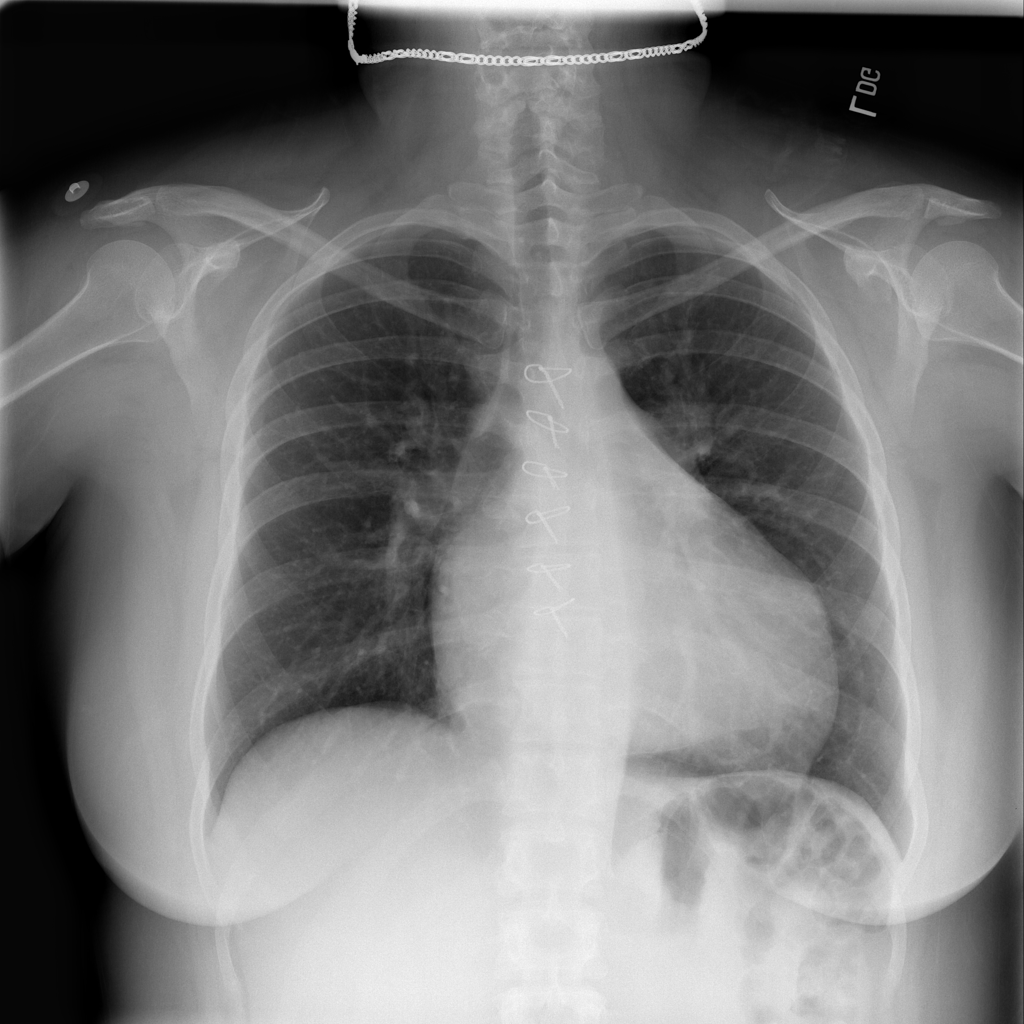

PAT-A5F7 · IMG-002Cardiomegaly

PAT-A5F7 · IMG-002

PA